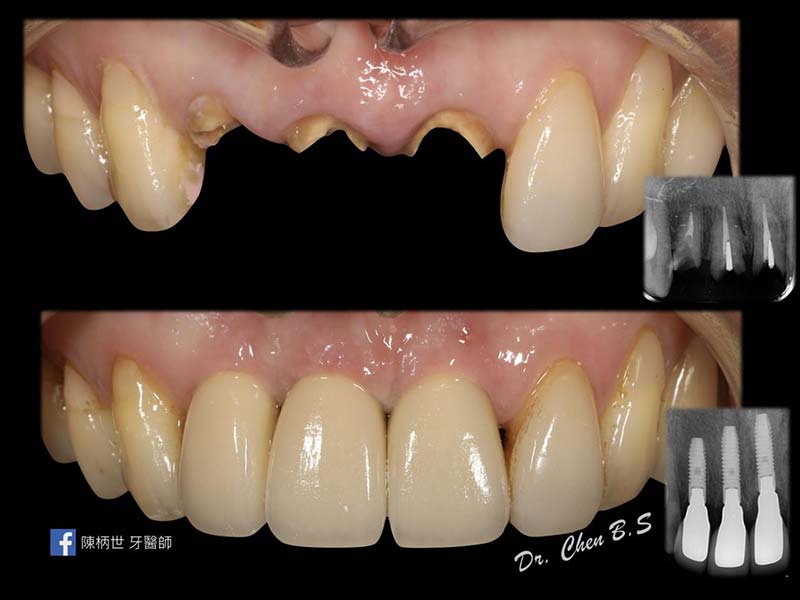

數位植牙

微創智齒手術